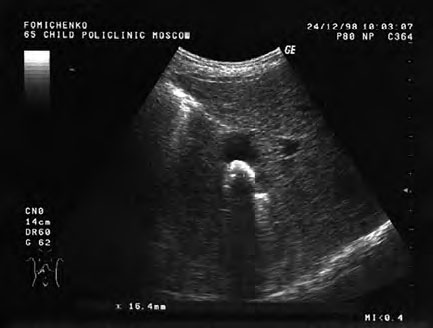

Ультразвуковое исследование, выполненное примерно через три недели проведения ежедневных лазеротерапевтических процедур, выявило уменьшение эхо-признаков воспалительной реакции в стенке желчного пузыря, абсолютную подвижность и незначительное уменьшение размеров конкремента: максимальный размер – 16,4 мм. При этом отмечено некоторое изменение эхо-структуры конкремента (рис. 28).

Рис. 28. Контрольное (второе) ультразвуковое исследование желчного пузыря больной Т. Ф-ко